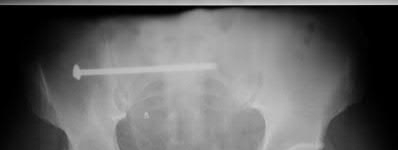

A 44-year-old male presents after being struck by a car. He is hypotensive, and has an obvious open tibia and a closed femoral shaft fracture. A pelvic radiograph is obtained and shown in Figure A. A representative CT scan image in shown in Figure B. The patient is placed in a pelvic binder, and his blood pressure normalizes with crystalloid and a blood transfusion. He then undergoes pelvic angiography, and his internal iliac artery is embolized. Which of the following definitive treatment options is most appropriate in this case?

The radiographs and CT scan show a fracture pattern consistent with an APC-III injury. This is most appropriately treated with pubic symphysis ORIF with a multi-hole plate and posterior iliosacral screw fixation.

APC-III pelvic ring injuries are associated with with disruption of the anterior and posterior SI ligaments (SI dislocation) as well as disruption of

sacrospinous and sacrotuberous ligaments. They are commonly associated with vascular injury and retroperitoneal bleeding.

Sagi et al studied the radiographic and clinical outcome of symphyseal plating techniques, specifically comparing two hole (THP) vs multi-hole plating (MHP). Retrospective review of charts and radiographs immediately after the index procedure to latest follow-up was performed. When comparing the 2 different methods of anterior fixation, they found that the rate of fixation failure was greater in group THP (33%) than group MHP (12%). When evaluating the presence of a malunion as a result of these 2 treatment methods, there were more present in the THP group (57%) than in the MHP group (15%). On the basis of these findings, the authors recommended multi-hole plating of unstable pubic symphyseal disruptions.

Grimshaw et al performed a biomechanical study to determine the failure risk and potential benefit to use of locked fixation constructs in simulated pelvic ring injuries. The authors used a six-hole 3.5-mm plate specifically designed for the symphysis pubis with the capability of fixation in locked or unlocked mode, six pelves were fixed with locked screws and six pelves were fixed standard unlocked bicortical screws. Biomechanical testing was performed, and no abrupt failures were noted. However, locked plating of the pubic symphysis did not appear to offer any advantage over the standard unlocked technique

Illustrations A, B, and C show the AP, outlet, and inlet postoperative radiographs.